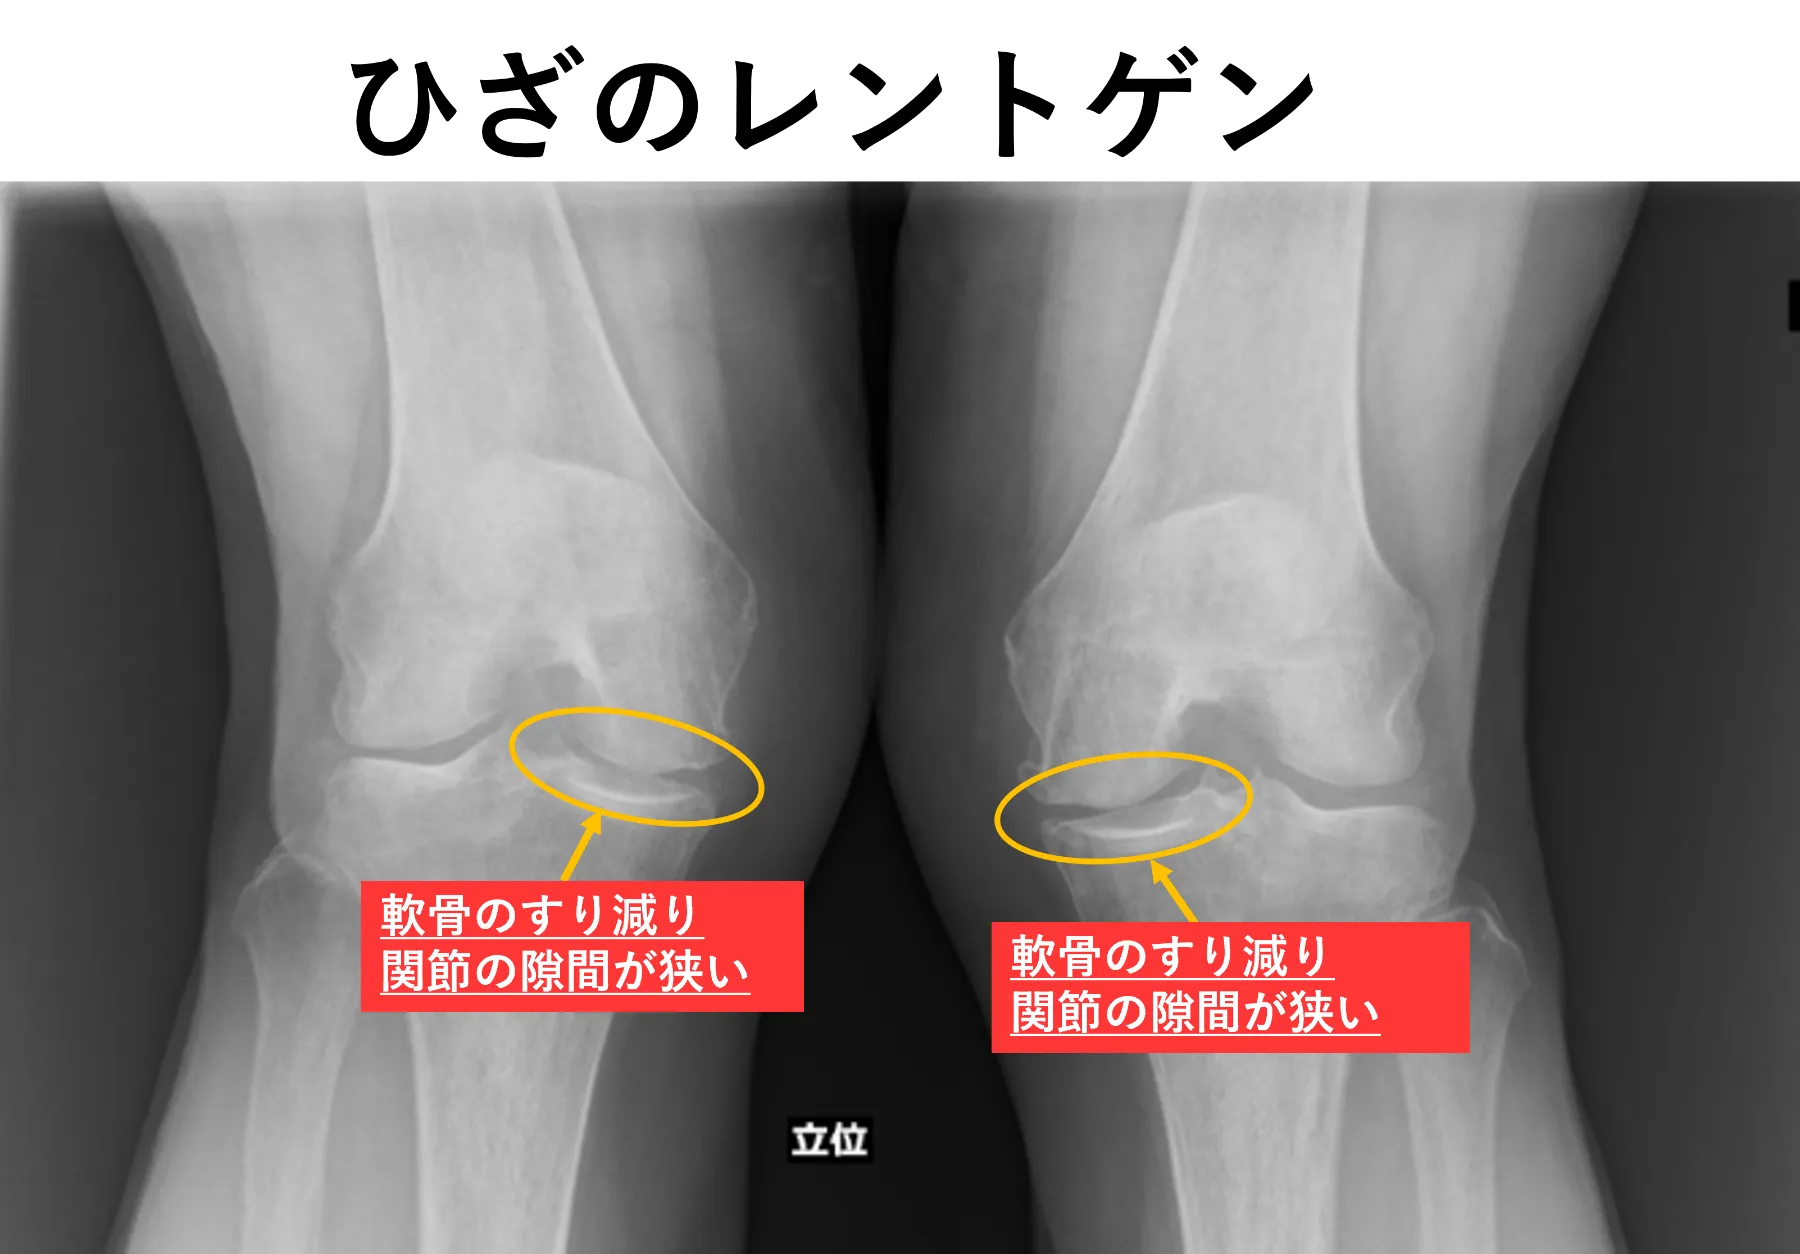

両変形性膝関節症、右変形性股関節症

MRI所見で右変形性股関節症、両変形性肩関節症を認めました。